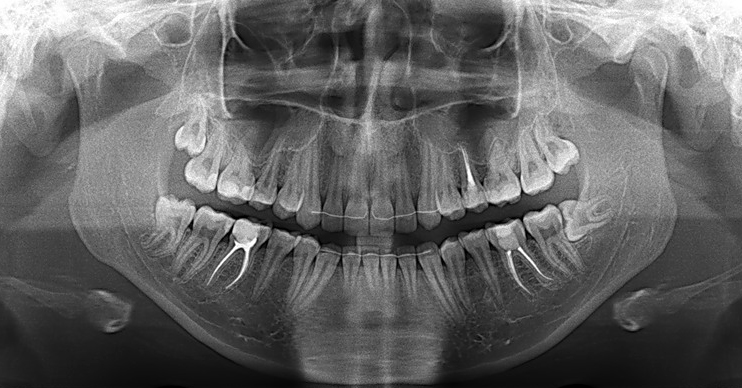

Технологические достижения: Planmeca и ОПТГ